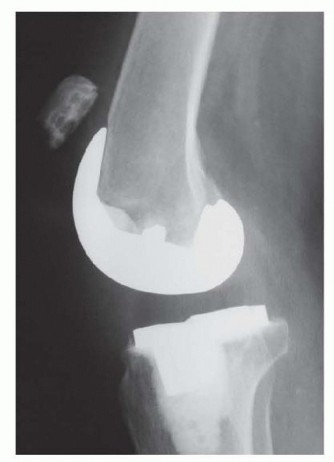

DEFINITION Bone loss and indications for the use of metallic augments in revision total knee arthroplasty (TK…

Indications Hinged total knee arthroplasty is utilized as a salvage procedure for complex primary or revision…